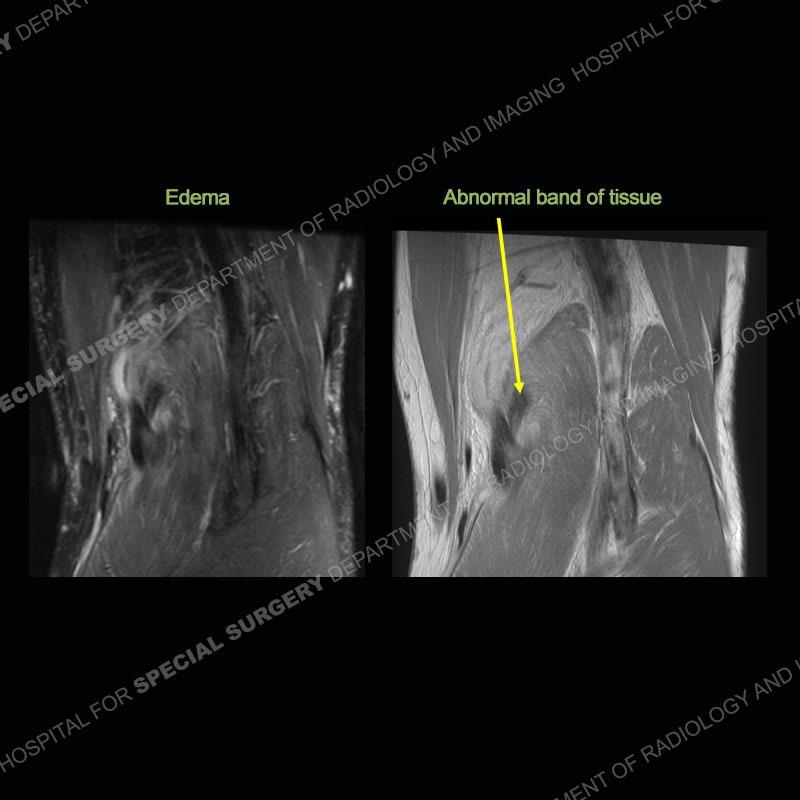

The radiographs show degenerative change of the medial compartment and a varus knee, but they are not germane to this case. No acute bony injury is present. The MRI shows edema of the posterior medial knee/soft tissue and a focal area of a partially disrupted low signal structure. The details are kept at a minimum in the findings of this case on purpose.

Diagnosis: Partial Disruption Medial Head Gastrocnemius (MHG)

The findings were kept purposefully vague as identifying the structures early on takes away a lot of the diagnosis. An uncommon entity and one of which we do not see a lot. Enthesopathic changes and tendinosis are seen as are distal MHG injuries, but proximal tears are rarely present. This case highlights a number of points. One, it almost always comes down to anatomy. Perhaps not a structure we normally spend too much time on, except save for diagnosing a Baker’s cyst, but knowing where this structure and all structures exist in all three planes is imperative. Second, when you think you are making a “call” or finding that you have never made before, step back and think is this just the abnormal presentation of a common pathology. That situation arises much more frequently. Third, if you look at it once, twice, and probably a third time and are confident in your odd or very rare diagnosis, stick to your guns. Especially, when it comes down to anatomic structures, the proof will be in the images.

Fourth, use all imaging planes and different pulse sequences to make your diagnosis. The edema highlighted in this case can be seen as the obscuration of fat on the PD images but is much easier to perceive as the high signal on the IR pulse sequences. The actual disruption of the MHG myotendinous junction is only able to be seen on the axial images. On the sagittal and coronal images, we get a sense something is wrong but hard to be exact. Lastly, when you look at a study and something just seems off (as I would say the sagittal and coronal images do with that dark band of tissue posteriorly), listen to yourself and go through the study slowly and meticulously. Most of the time you will find you were right, and something indeed is present.